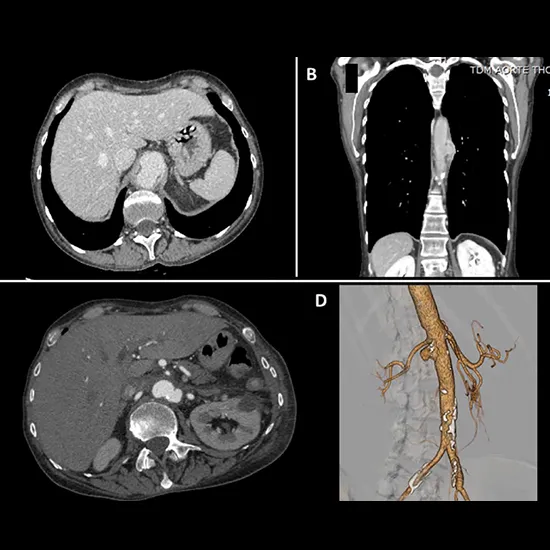

A CT Abdominal Aorta is an imaging procedure that examines your aortic vessels.

CT scans the body in cross-section, including the aorta, using X-rays. It can detect an aneurysm's size and shape. You typically lie on a table inside a doughnut-shaped X-ray machine during a CT scan. A dye (contrast) may be administered intravenously to help the arteries show up more clearly on the X-ray.

In this procedure, you must lie supine on the table with your arm on the side. An IV line is inserted in your arm, and dye is injected through the IV line (90-100ML) while the scan is being performed. It is possible that you will be asked to hold your breath for a few seconds.